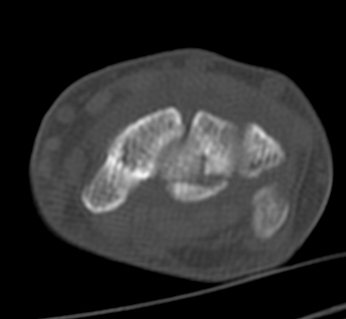

ÃÊÀ½ÆÄ°Ë»ç : ¼Õ¸ñ ¹èÃø Á¾´Ü¸é°Ë»ç¿¡¼­ ¼ö±Ù°üÀý³» ¼ö¾×Àú·ù°¡ °üÂûµÊ(»çÁø 1).